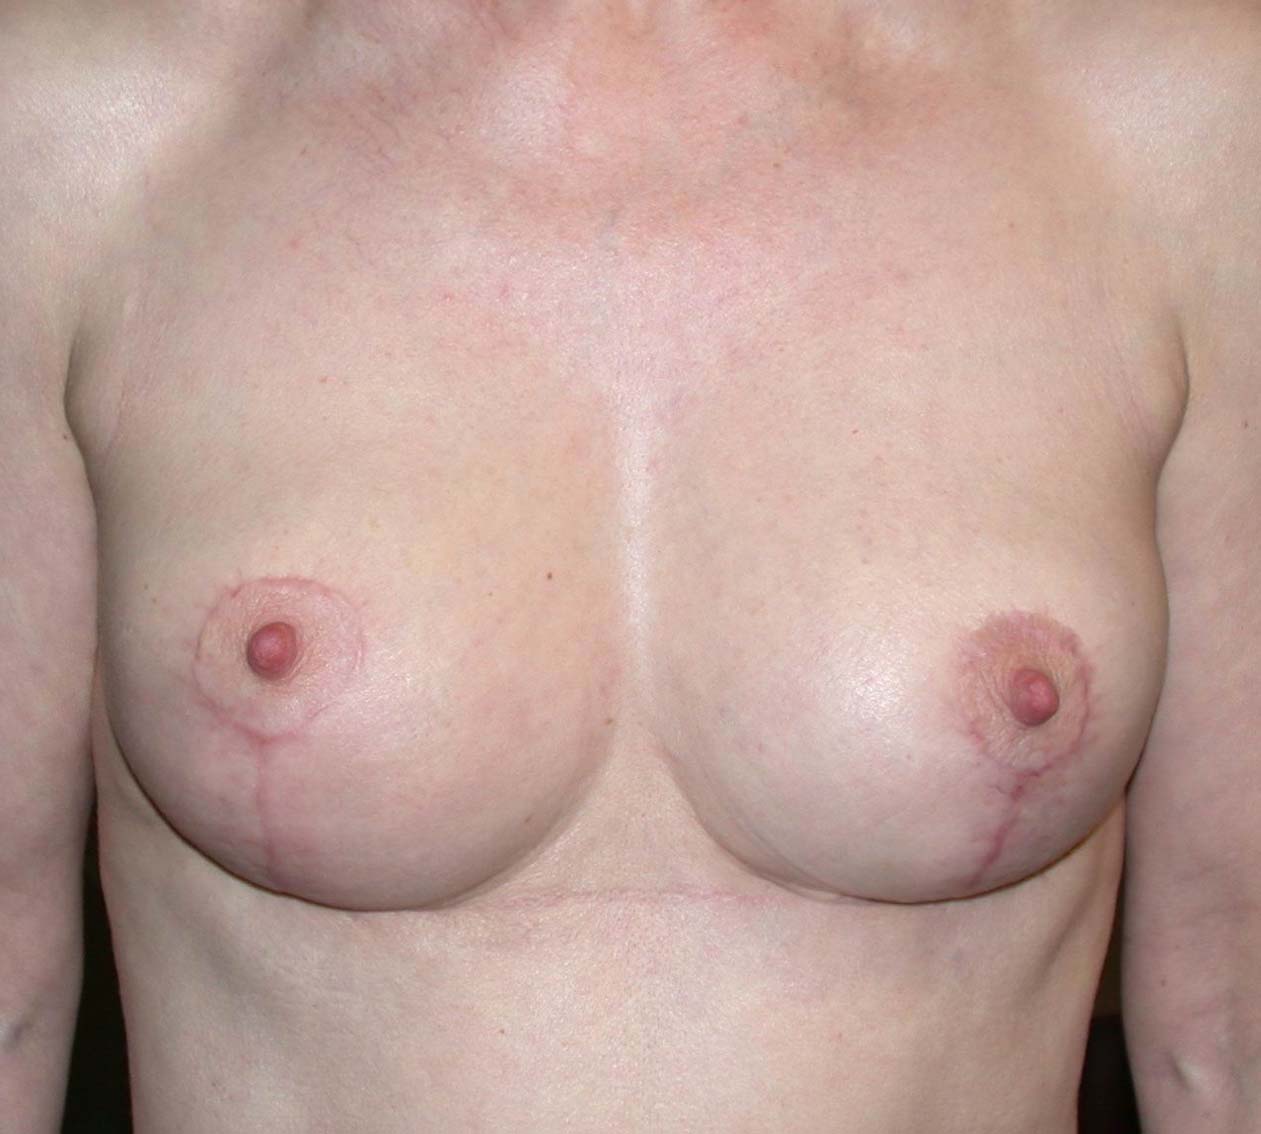

Cet album contient des exemples de plasties mammaires de correction de ptôse sans adjonction ou diminution de volume du sein. Seul le tissu mammaire présent est remodelé et repositionné. Le volume des seins est identique avant et après l’intervention.